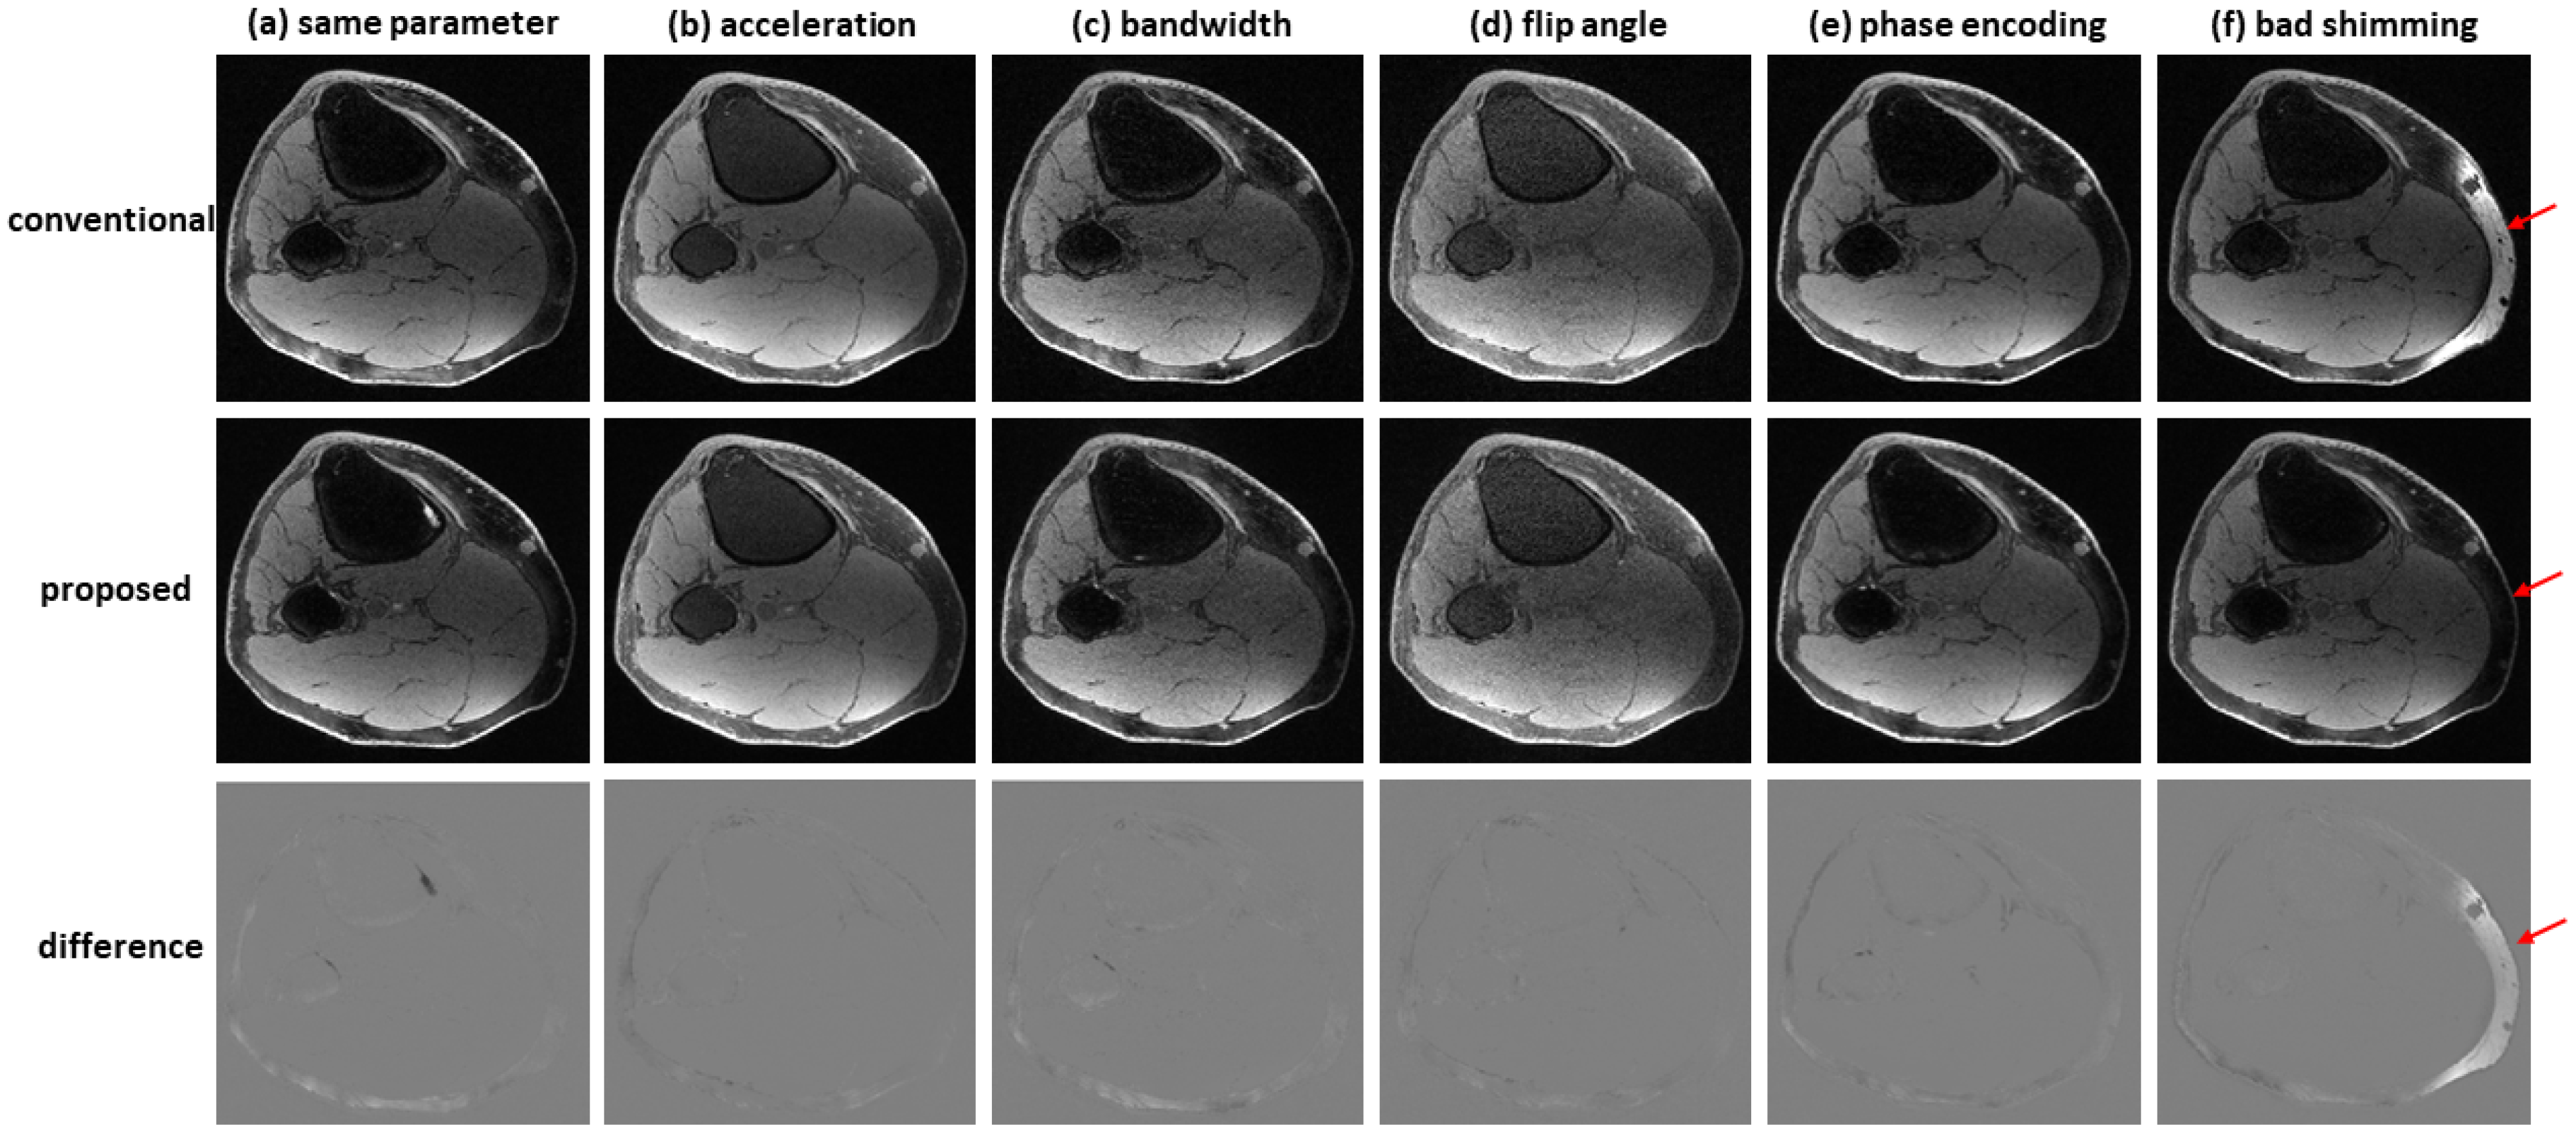

Figure 7 shows an example of water–fat separation from non-contrast-enhanced dual-echo images using a model trained with contrast-enhanced images. Even if the imaging parameters were slightly different from those adopted in contrast-enhanced studies (with an acceleration factor of 2, bandwidth of 83.3 kHz, flip angle of 25°, or phase encoding of 224), the predicted images had high fidelity to the reference images, indicating the proposed method has high potential to support flexible imaging parameters. When bad shimming was intentionally imposed (to generate highly inhomogeneous field), water/fat swaps that occurred in reference images were corrected in the predicted images.

Figure 7.

Water–fat separation from non-contrast-enhanced dual-echo images using a model trained with contrast-enhanced images. The non-contrast-enhanced dual-echo images were acquired using (a) the same imaging parameters as those adopted in contrast-enhanced studies, (b) an acceleration factor of 2, (c) bandwidth of 83.3 kHz, (d) flip angle of 25°, and (e) phase encoding of 224. In these cases, the predicted images had high fidelity to the reference images. (f) When bad shimming was intentionally imposed, water/fat swaps that occurred in the reference image were corrected in the predicted image.